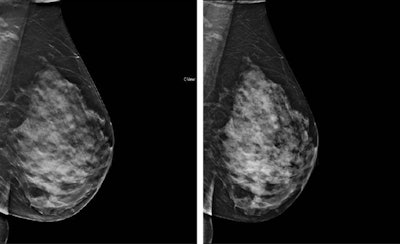

Synthetic 2D images derived from digital breast tomosynthesis (DBT) are comparable with full-field digital mammography (FFDM), according to Spanish researchers. Furthermore, synthetic images could replace FFDM in studies that use both modalities and reduce radiation dose by 45%, they said.

The study team compared synthetic 2D images with FFDM in terms of lesion detectability and BI-RADS lesion categorization. The group, led by Dr. Julia Garayoa from the radiological protection unit at Hospital Universitario Fundación Jiménez Díaz in Madrid, found synthetic images are "not inferior" to FFDM.

As DBT gains in popularity, the question becomes more and more: Can radiologists ditch FFDM? Most studies examine DBT plus FFDM, but few compare synthetic 2D images with FFDM alone, without access to DBT, to see how synthetic 2D fares.

Garayoa and colleagues sought to evaluate the clinical performance of synthetic images alone compared with FFDM alone in terms of lesion detectability and BI-RADS lesion categorization.